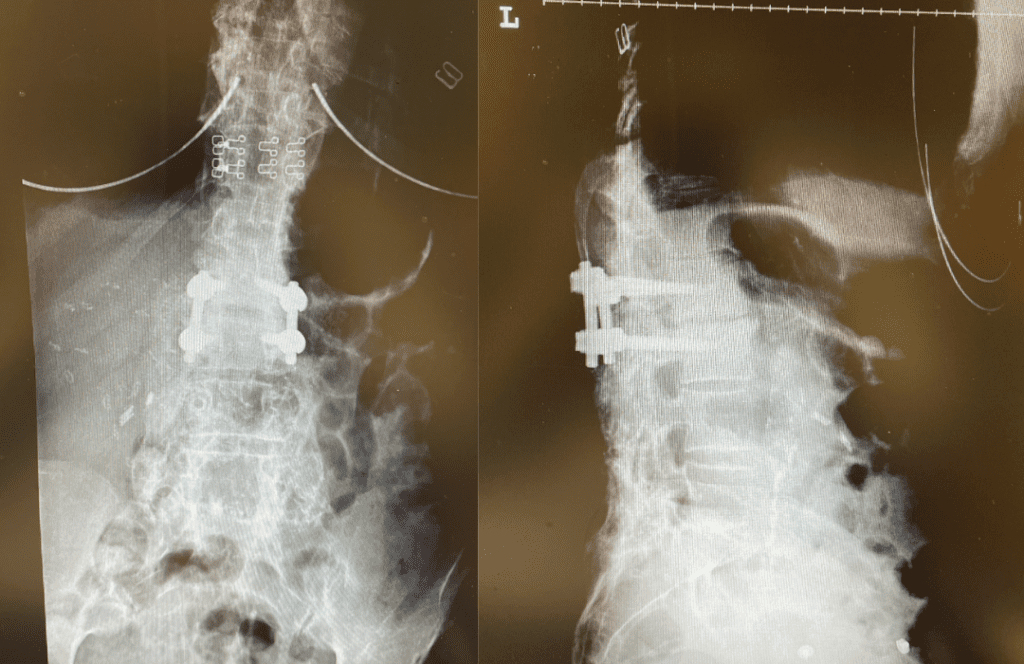

Figure 2. Axial T2 MRI of the lumbar spine demonstrating L2-3 stenosis due to significant facet arthropathy.